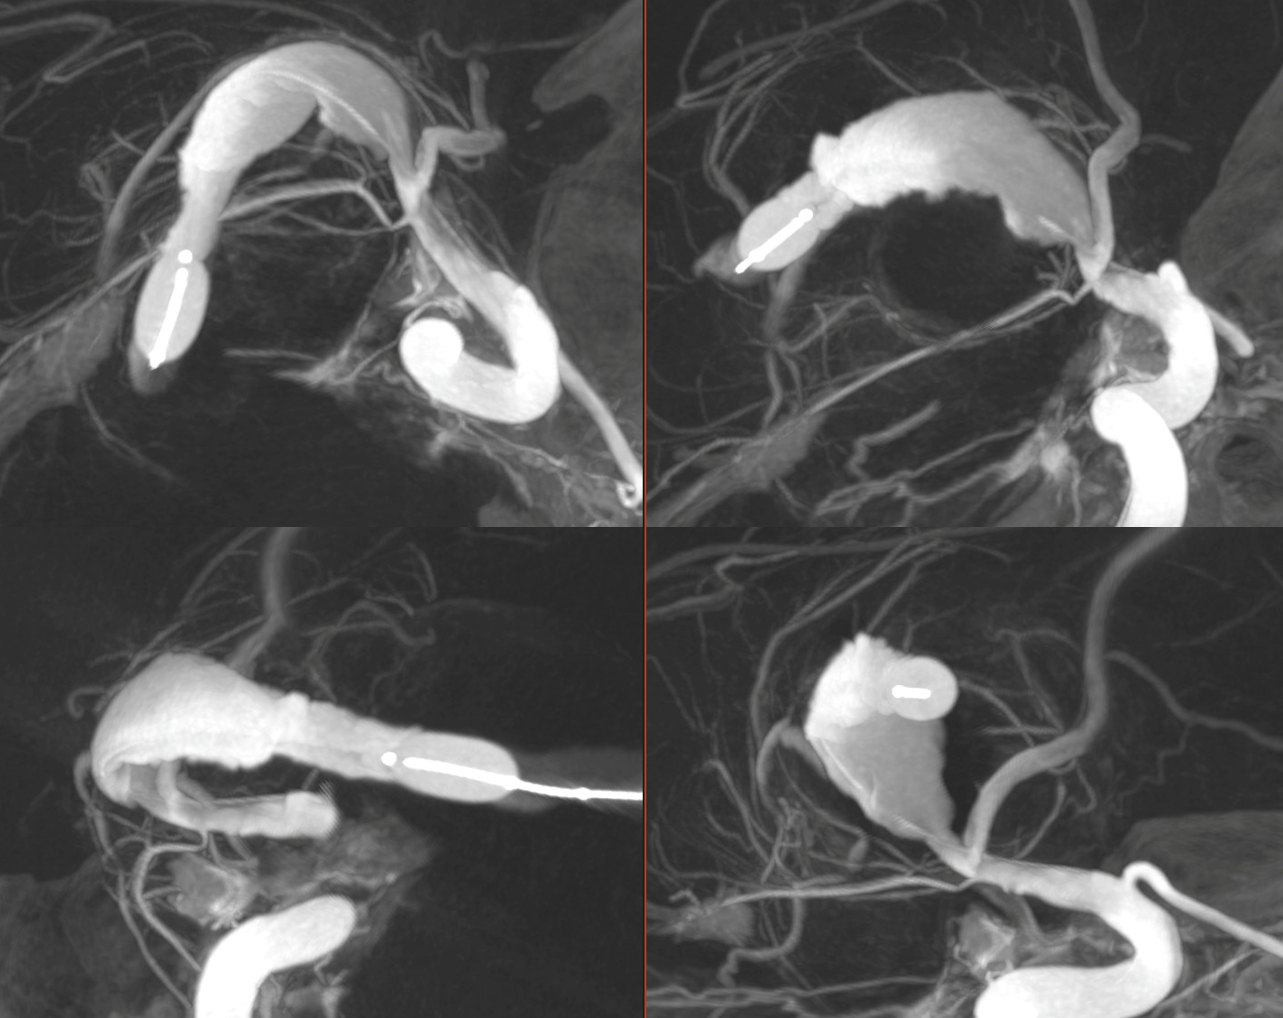

The question is where are the lenticulostriate and insular perforators?

A dual lumen compliant balloon was inflated in the distal segment of the serpentine aneurysm and a Vaso-CT (22 cm FOV, 20 seconds acquisition) was acquired manually injecting pure contrast (300 mg/ml) in the ICA with a 20 ml syringe. It was done to be sure that no perforating arteries originate between the anterior choroidal artery and the bypass. Note the thin metallic filament of the non-radiopaque part of the microguidewire.

Another Vaso-CT was acquired manually injecting pure contrast (300 mg/ml) in the bypass (the injection was visually modulated to avoid reflux in the ICA), maintaining the balloon in place. It clearly shows the M2 perforators originating after the conjunction of the bypass.